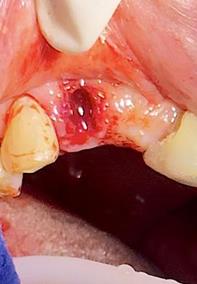

Figura 6. Sindesmotomía, luxación y prensión del incisivo lateral superior derecho pieza N.º 1.2

Elaboración: Los autores.